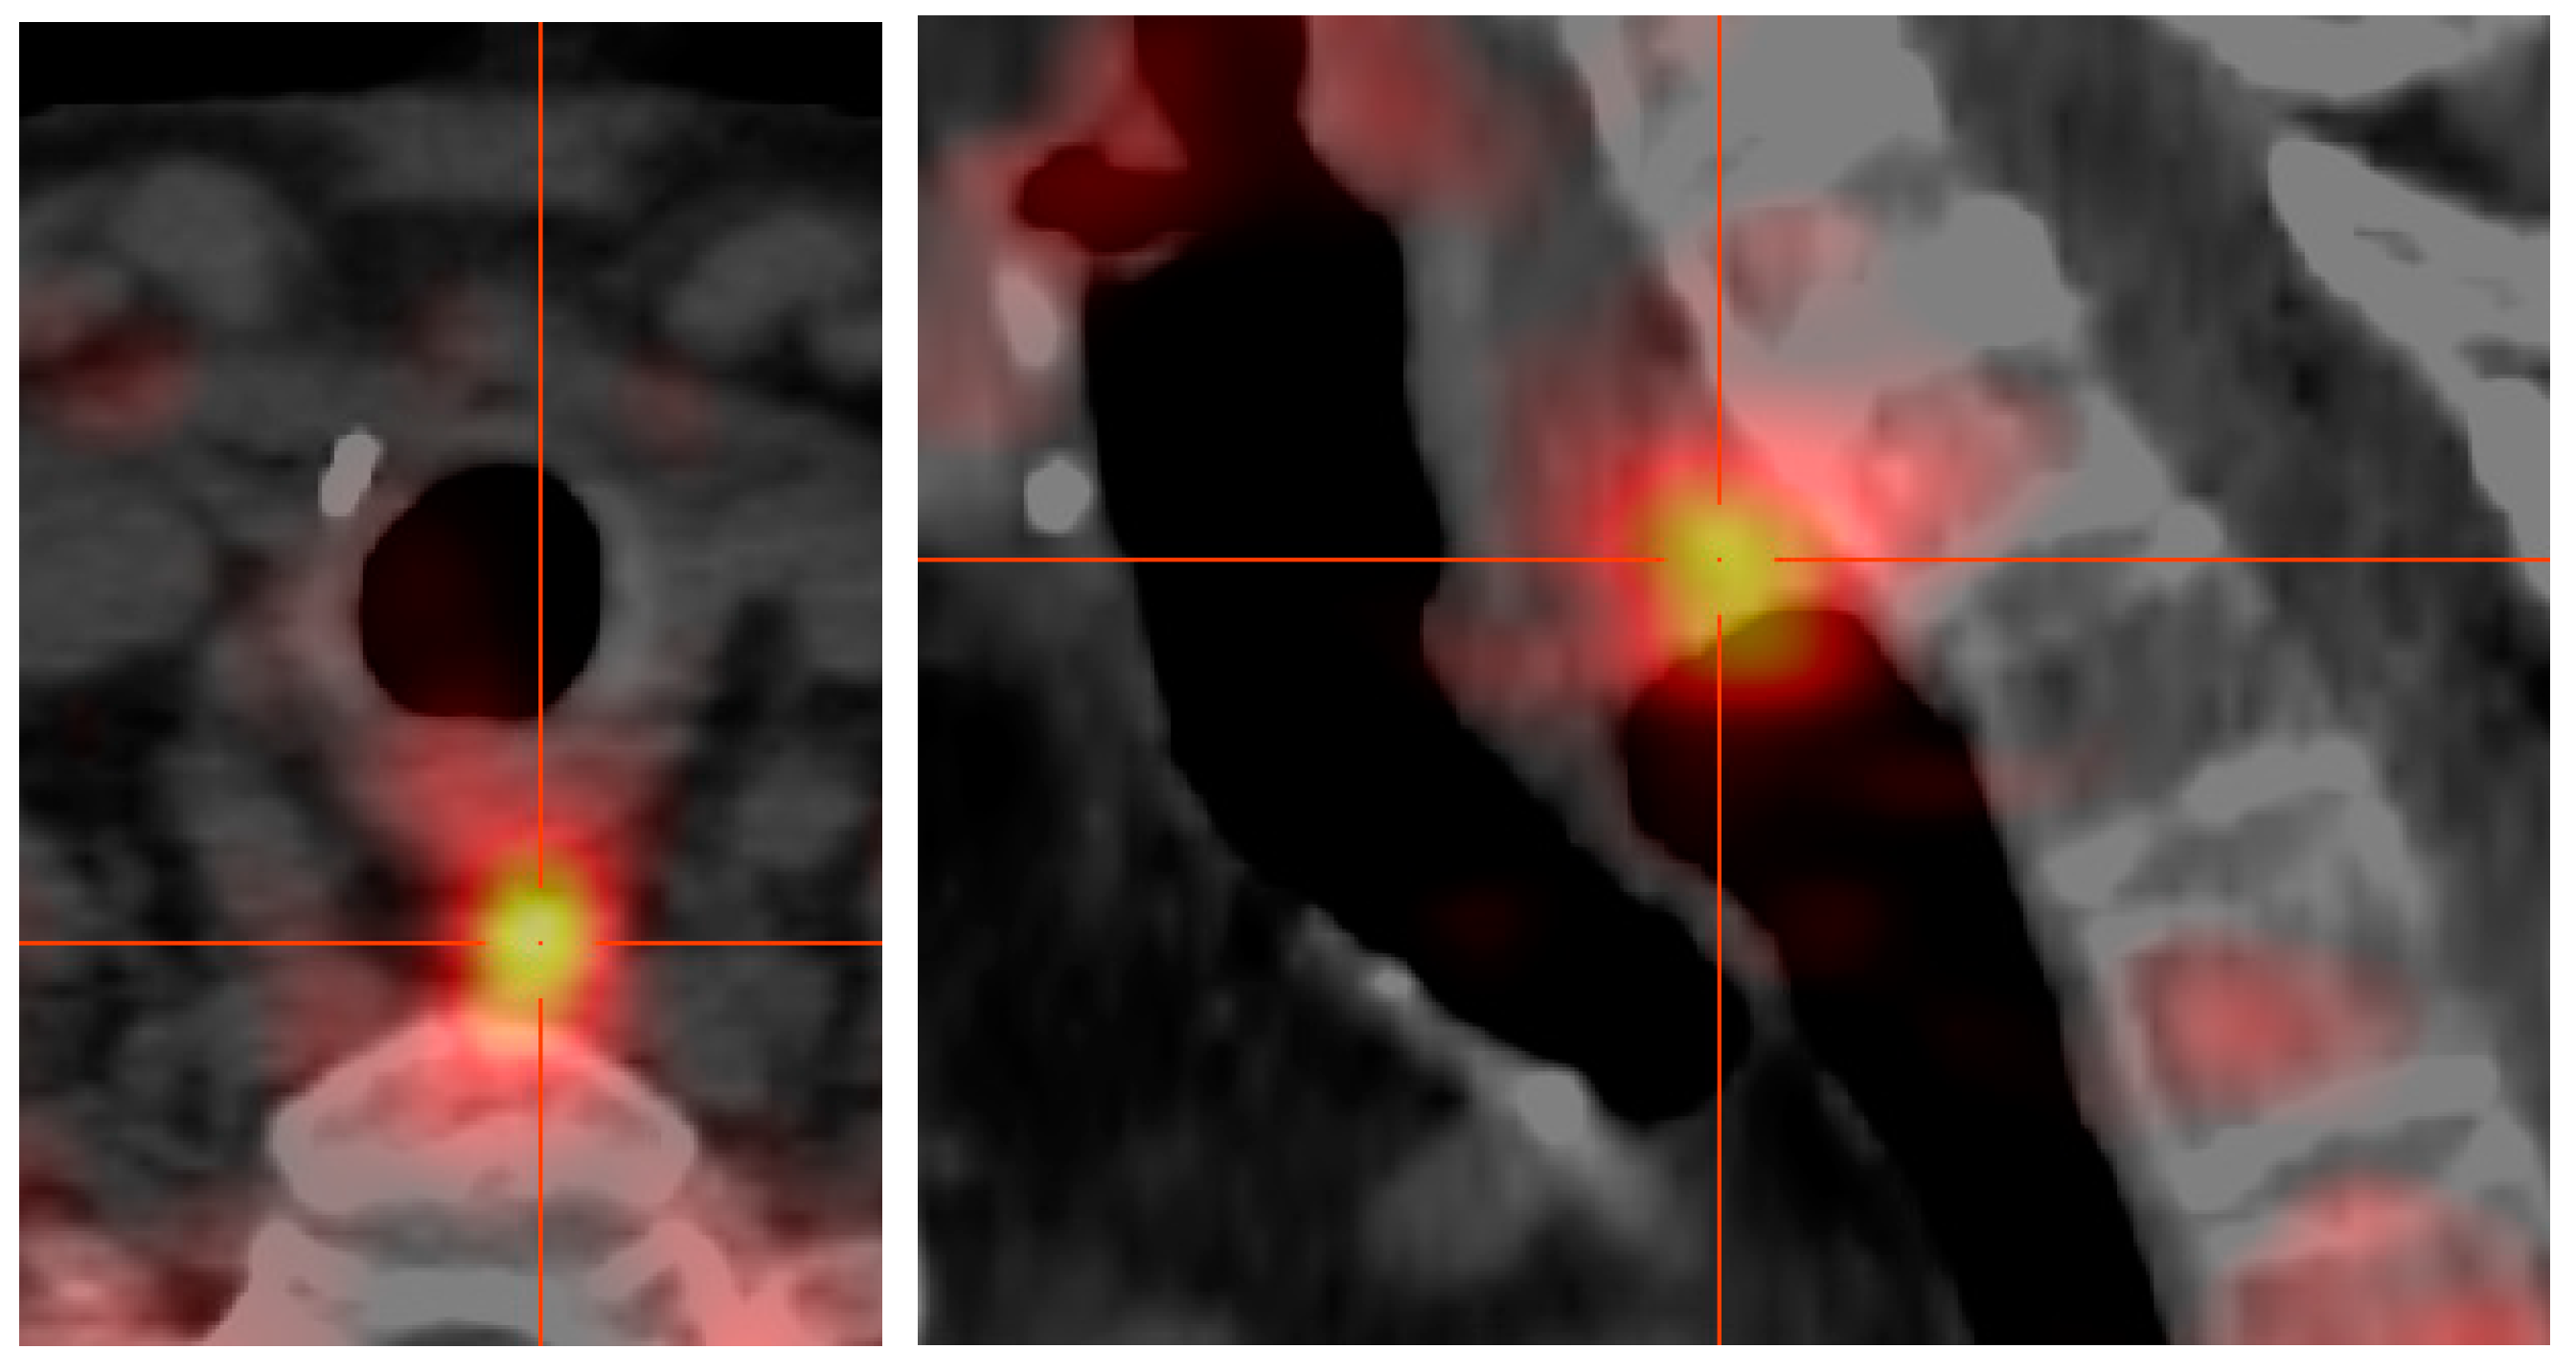

[18F]fluoro-ethylcholine-PET Plus 4D-CT (FEC-PET-CT): A Break-Through Tool to Localize the “Negative” Parathyroid Adenoma. One Year Follow Up Results Involving 170 Patients

2. Materials and Methods

3.2. Localization of PA by Ultrasound, MIBI-Scintigraphy and FEC-PET-CT plus 4D-CT